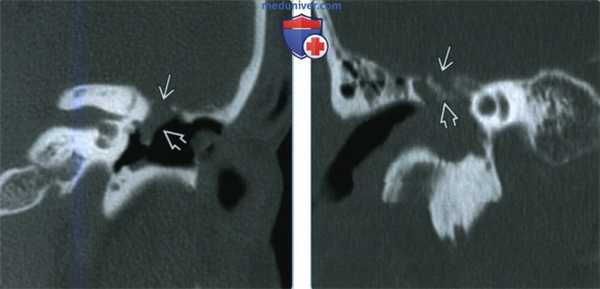

(Слева) При аксиальной КТ в костном окне у пациента с правосторонним параличом лицевого нерва визуализируется маленькая ВМЛН в ямке коленчатого ганглия. Обратите внимание на точечные костные очаги в структуре, которые позволяют отличить ВМЛН от шванномы лицевого нерва, которая также возникает преимущественно в ямке коленчатого ганглия.

(Справа) При аксиальной МРТ Т1 С+ FS у этого же пациента определяется ВМЛН, накапливающая контраст, в области коленчатого ганглия. Область точечных кальцинатов выглядит как гипоинтенсивный фокус.

(Слева) При аксиальной КТ правой височной кости определяется среднеразмерная ВМЛН в ямке коленчатого ганглия, распространяющаяся вдоль передневнутренней поверхности височной кости ВМЛН имеет типичную форму полумесяца, огибающего улитку с внутренней стороны на передней поверхности височной кости.

(Справа) При аксиальной МРТ Т1С+ у этого же пациента определяется диффузное контрастное усиление ВМЛН в ямке коленчатого ганглия, огибающее улитку вдоль передневнутренней поверхности височной кости.